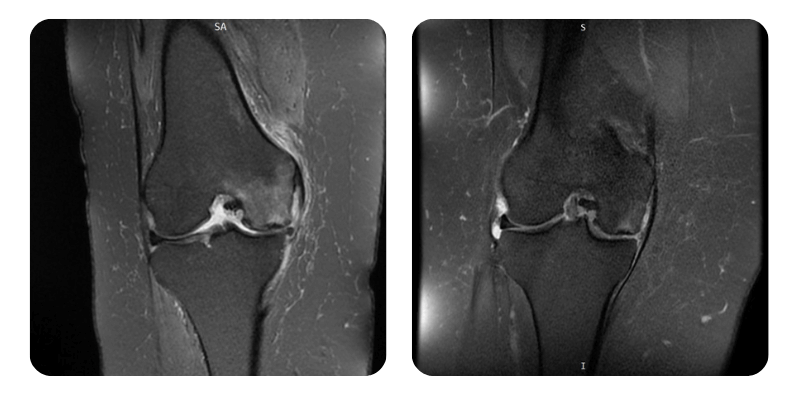

Prima

Dopo

P.V., 54 anni - Edema con focolaio di osteonecrosi del condilo femorale mediale destro

Prognosi: Edema ridotto di circa l'80%, confermato anche radiologicamente.